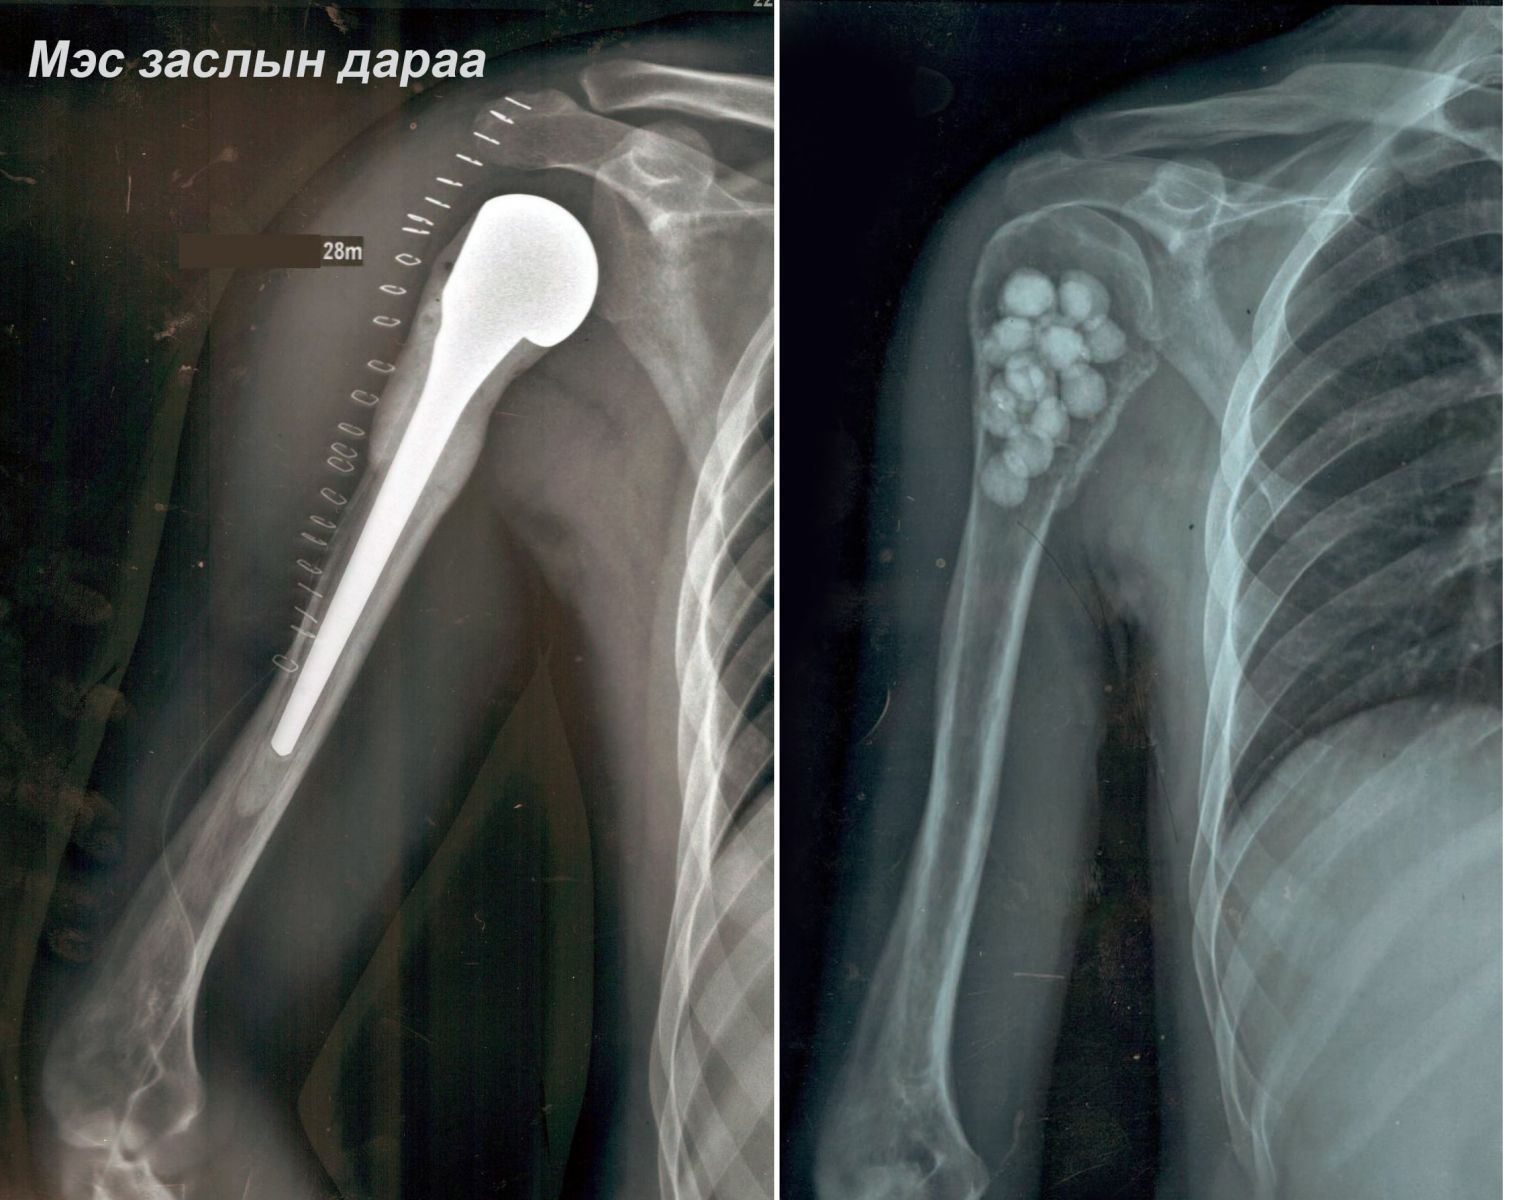

ГССҮТ, ХСҮТ-ийн ерөнхий мэс заслын эмч нар хамтран эрхтэн хадгалах мэс заслыг 2020 оны 21-ний амжилттай хийлээ. Тодруулбал, Эмчлүүлэгч 28 настай, эрэгтэйн баруун талын атгаал ясны дээд хэсгийн хорт хавдрыг авч баруун талын атгаал ясыг тайран мөрний үеийг сольсон эрхтэн хадгалах мэс засал хийсэн юм.